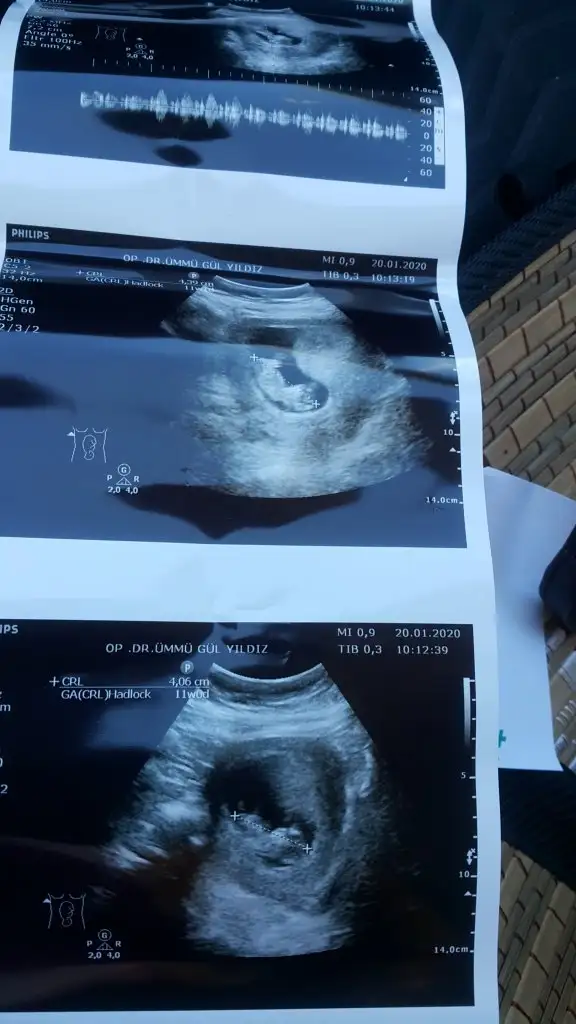

mrhaba lütfen yorumlarmisiniz sizce kızmı erkekmi bi arkadas icin soruyorum

Sevgili İkra,

Yorumlarsan çok sevinirim. ☺️❤️